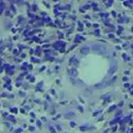

Leishmaniasis background and histology presentation. The World Health Organization (WHO) has selected cutaneous leishmaniasis as a neglected tropical disease (NTD) with growing, uncontrolled, and ignored infection affecting millions of people every year [14, 9]. It is unfortunately one of the world’s most neglected poverty-related diseases, affecting the poorest people in developing countries and it is associated with risk factors like malnutrition, immune system deficiency, migration, inadequate education, illiteracy, gender inequality, and a shortage of services [1]. Furthermore, only eight countries in the world contribute to 90% of leishmaniasis cases: Afghanistan, Algeria, Brazil, Iran, Pakistan, Peru, Saudi Arabia, and Syria [12]. It is a vector-borne infection caused by the protozoan parasite Leishmania. The vector is the female sand-fly. The lesions of cutaneous leishmaniasis vary in presentation ranging from a single self-limited skin lesion to multiple large destructive and ulcerated lesions on mostly the exposed parts of the body such as face, forearms, and lower legs [2]. Skin biopsy is considered the gold standard method for confirmation of diagnosis. The presence of large epitheloid granulomas and small hematoxylinophilic LD bodies (that are round, uniform in appearance, intracytoplasmic and sometimes distributed around the outer rim of the vacuoles) is critical for diagnosis and confirmation of leishmaniasis [4]. Large granulomas are visible at 10X but the smaller hematoxylinophilic bodies (around 3-4mm in size) are usually visible at 40X and can easily be missed if they are few in number, leading to misdiagnosis. Specialized dermatopathologists are the only ones who can diagnose these accurately based on patient history, clinical features, and laboratory diagnosis. It is thus critical to share the digitized slides of these cases from rural poor remote areas with dermatopathologists (mostly residing in urban centers) for quick diagnosis and accurate management of the patient.

We demonstrate our WSI creation workflow on Leishmaniasis cases, as shown in Figures 1 and 4. An expert pathologist reviewed the cases and annotated granulomas as well as LD bodies on the stitched images and our generated images in Figure 4. To show generalizability of our approach, we also show results on core biopsies of breast, duodenum, stomach, liver, and lymph nodes (Figure 5).